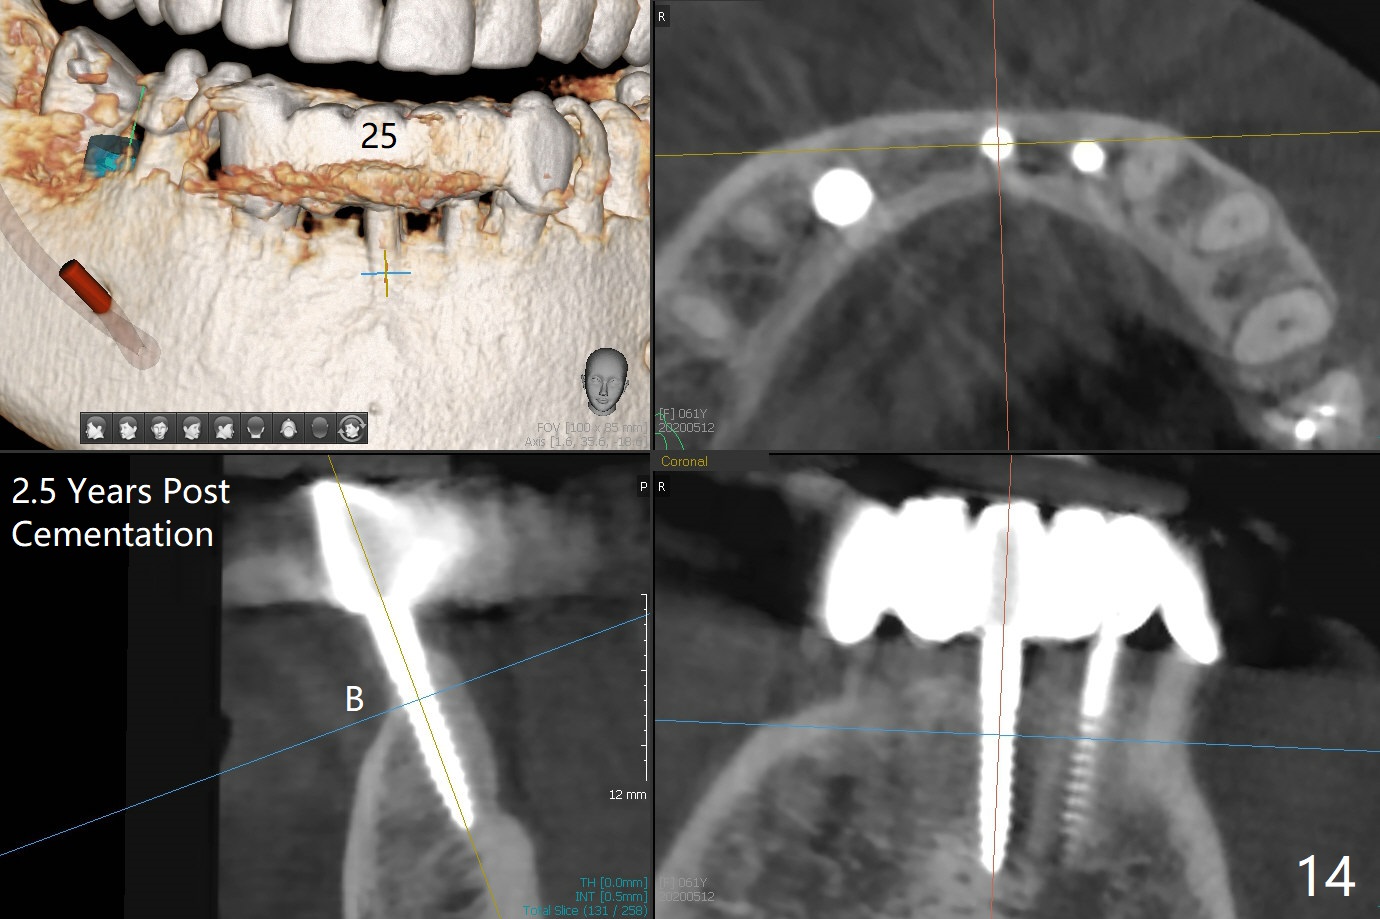

The mesial defect at #27 appears to have been repaired 8 months postop (Fig.8,9 *); there is no bone loss at 1-piece implant sites. The gingival recession seems to remain the same before and after removal of the provisional FPD (Fig.10,11). The bulging abutment at the cervix is less prominent when a straight abutment is used and prepared (Fig.12, 4.5x5.5(5) mm). There is no bone loss at #23, 25 and 27 sites 2.5 years post cementation (Fig.12-15), although the trajectory of the implants could be improved by using surgical guide (Fig.16-18).